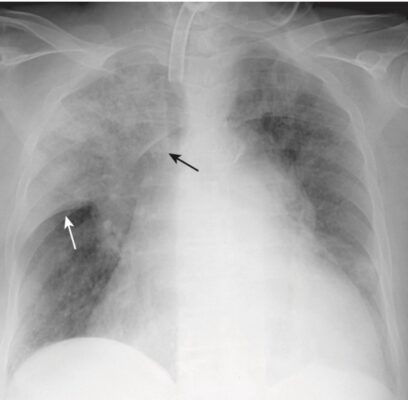

- Điển hình biểu hiện là một viêm phổi kẽ dạng lưới, quanh rốn phổi hoặc như một bệnh khoảng chứa khí có thể trông giống như dạng phân bố trung tâm của phù phổi (Hình 5).

- Các biểu hiện khác, chẳng hạn như bệnh khoảng chứa khí một bên hoặc bệnh khoảng chứa khí loang lổ ít phổ biến hơn.

- Thường không có tràn dịch màng phổi và không có hạch rốn phổi